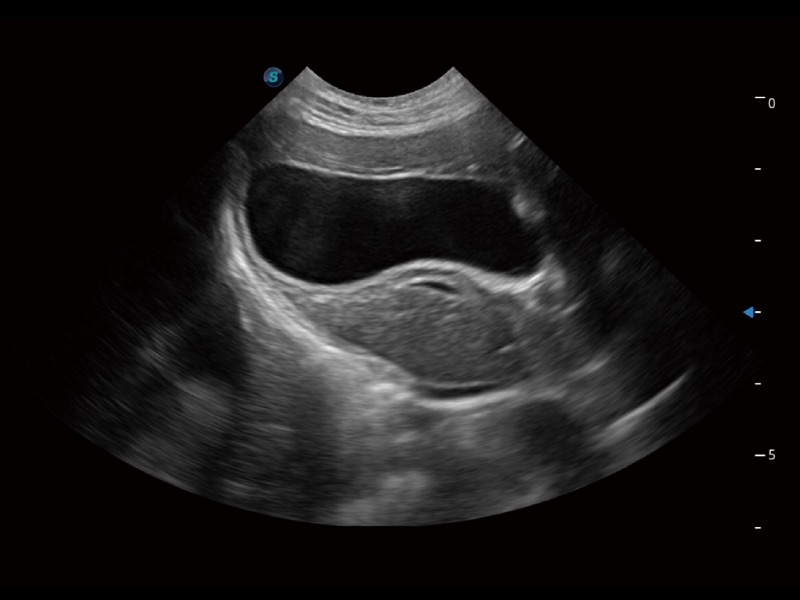

优异的基础图像

ProPet 70 全新的动物超声智能软件和丰富的探头群,为动物医生提供了高清晰度和精细分辨率的图像,无论在宠物、马科、畜牧还是实验室动物等应用中都可以轻松应对,为您的日常工作带来满意的体验。

(猫)胆囊